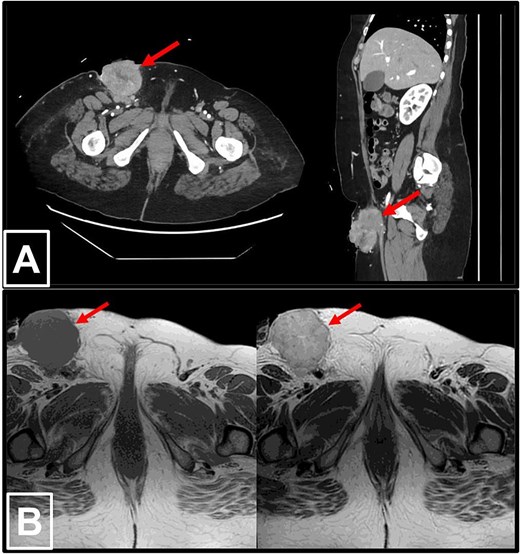

Laboratory tests showed an elevated CA-125 level of 531.7 U/mL. Contrast-enhanced computed tomography (CT) and magnetic resonance imaging (MRI) of the abdomen and pelvis depicted a large necrotic right inguinal mass measuring 5.3 × 6.2 × 8.5 cm, ulcerating into the skin, and closely abutting adjacent inguinal vessels. No significant intra-abdominal lymphadenopathy or thoracic metastases were detected (Fig. 1).

Radiological imaging of the right inguinal mass. (a) Contrast-enhanced CT scans of the abdomen and pelvis in axial (left) and sagittal (right) views, demonstrating a pathologically enlarged necrotic right inguinal lymph node (red arrow), measuring 5.3 × 6.2 × 8.5 cm. The mass is ulcerating into the inguinal skin and is in very close proximity to the adjacent inguinal vessels. (b) MRI of the pelvis in T1-weighted (left) and T2-weighted (right) sequences, again revealing the pathologically enlarged necrotic right inguinal lymph node (red arrow).